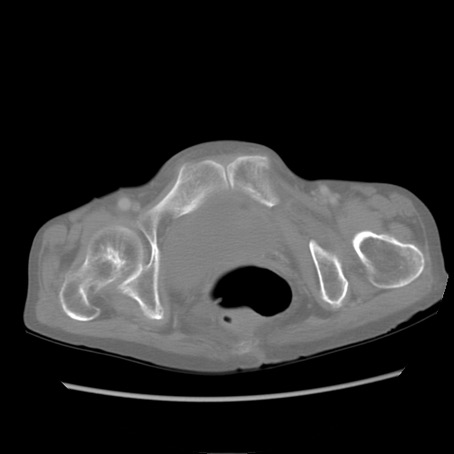

冠状断像

【症例】80歳代女性

【主訴】胸のつかえ感

【現病歴】約9時間前に食後から胸のつかえた感じあり、嘔吐あり、来院。

【既往歴】胃癌(全摘)、胆摘、虫垂炎

【身体所見】心窩部に圧痛あり、反跳痛なし。

【データ】WBC 5700、CRP 0.05